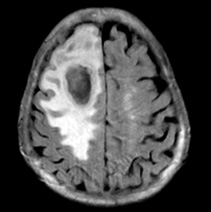

【脳膿瘍】

脳膿瘍とは、病原体が脳実質に化膿を起こし、膿汁が貯留した状態を指します。

原因として、血液中に菌が蔓延している状態であったり、中耳炎や副鼻腔炎、歯髄炎など脳に近い領域の感染症が代表的です。

症状は、発熱と頭痛、嘔気・嘔吐に加えて、膿汁が溜まっている部位に一致した神経症状(視野障害や失語症、片方の手足の麻痺や感覚障害など)です。

治療法はまず強力な抗生剤による保存的加療を行います。抗生剤の効果が弱い場合には手術を行い、膿汁を排液(排膿)します。

治療成績は以前に比べると改善しておりますが、現在においても致死率は10%程度とされています。